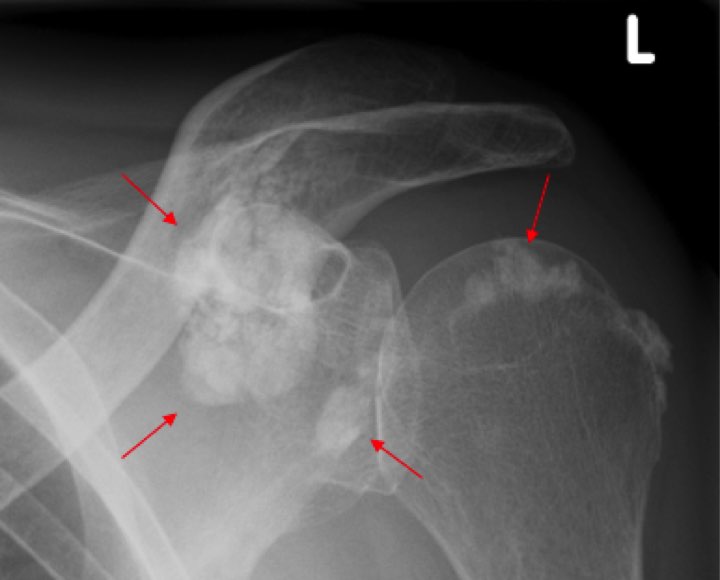

When the pain persisted, clinicians ordered lab tests, which revealed a phosphate level of about 1.20 mmol/L. An X-ray examination of his left shoulder (Figure) showed evidence of severe ectopic or metastatic calcification (red arrows) around the joint structures of his left shoulder.

Figure. A 46-year-old male patient with ESRD and painful motion of the left shoulder. X-ray examination showed metastatic calcification (red arrows) around the joint structures of the left shoulder.